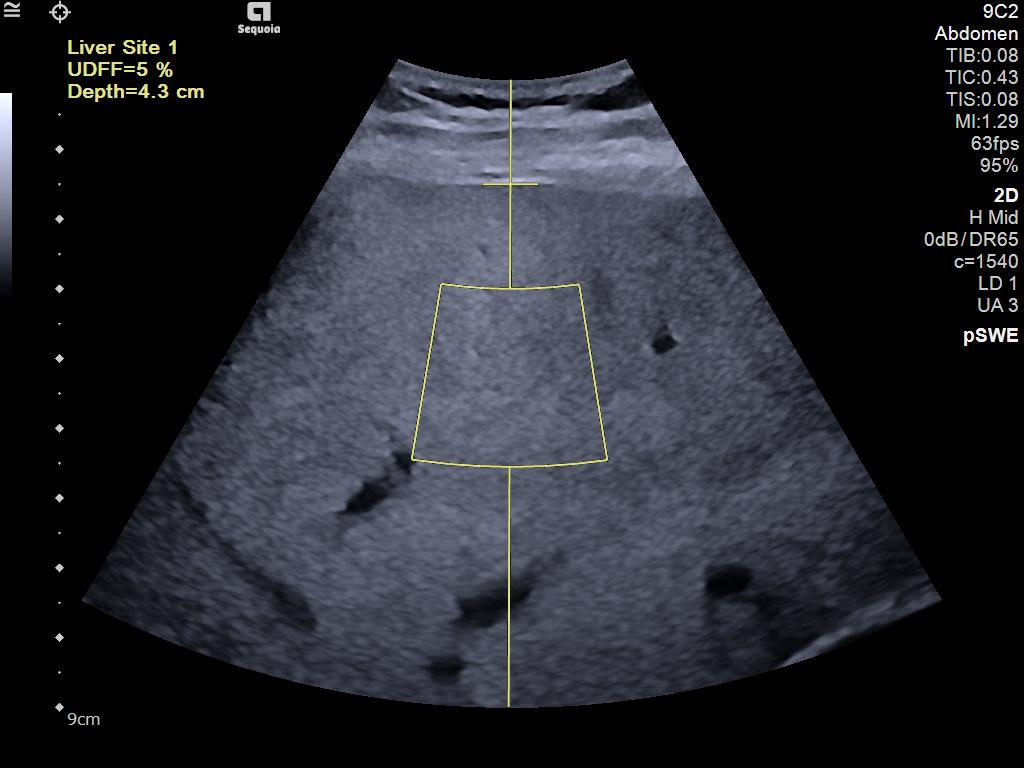

- Ultrasound Derived Fat Fraction (UDFF) for quantitative ultrasound for liver disease assessment.

- Auto pSWE to reduce liver elastography exam time by up to 75%*.